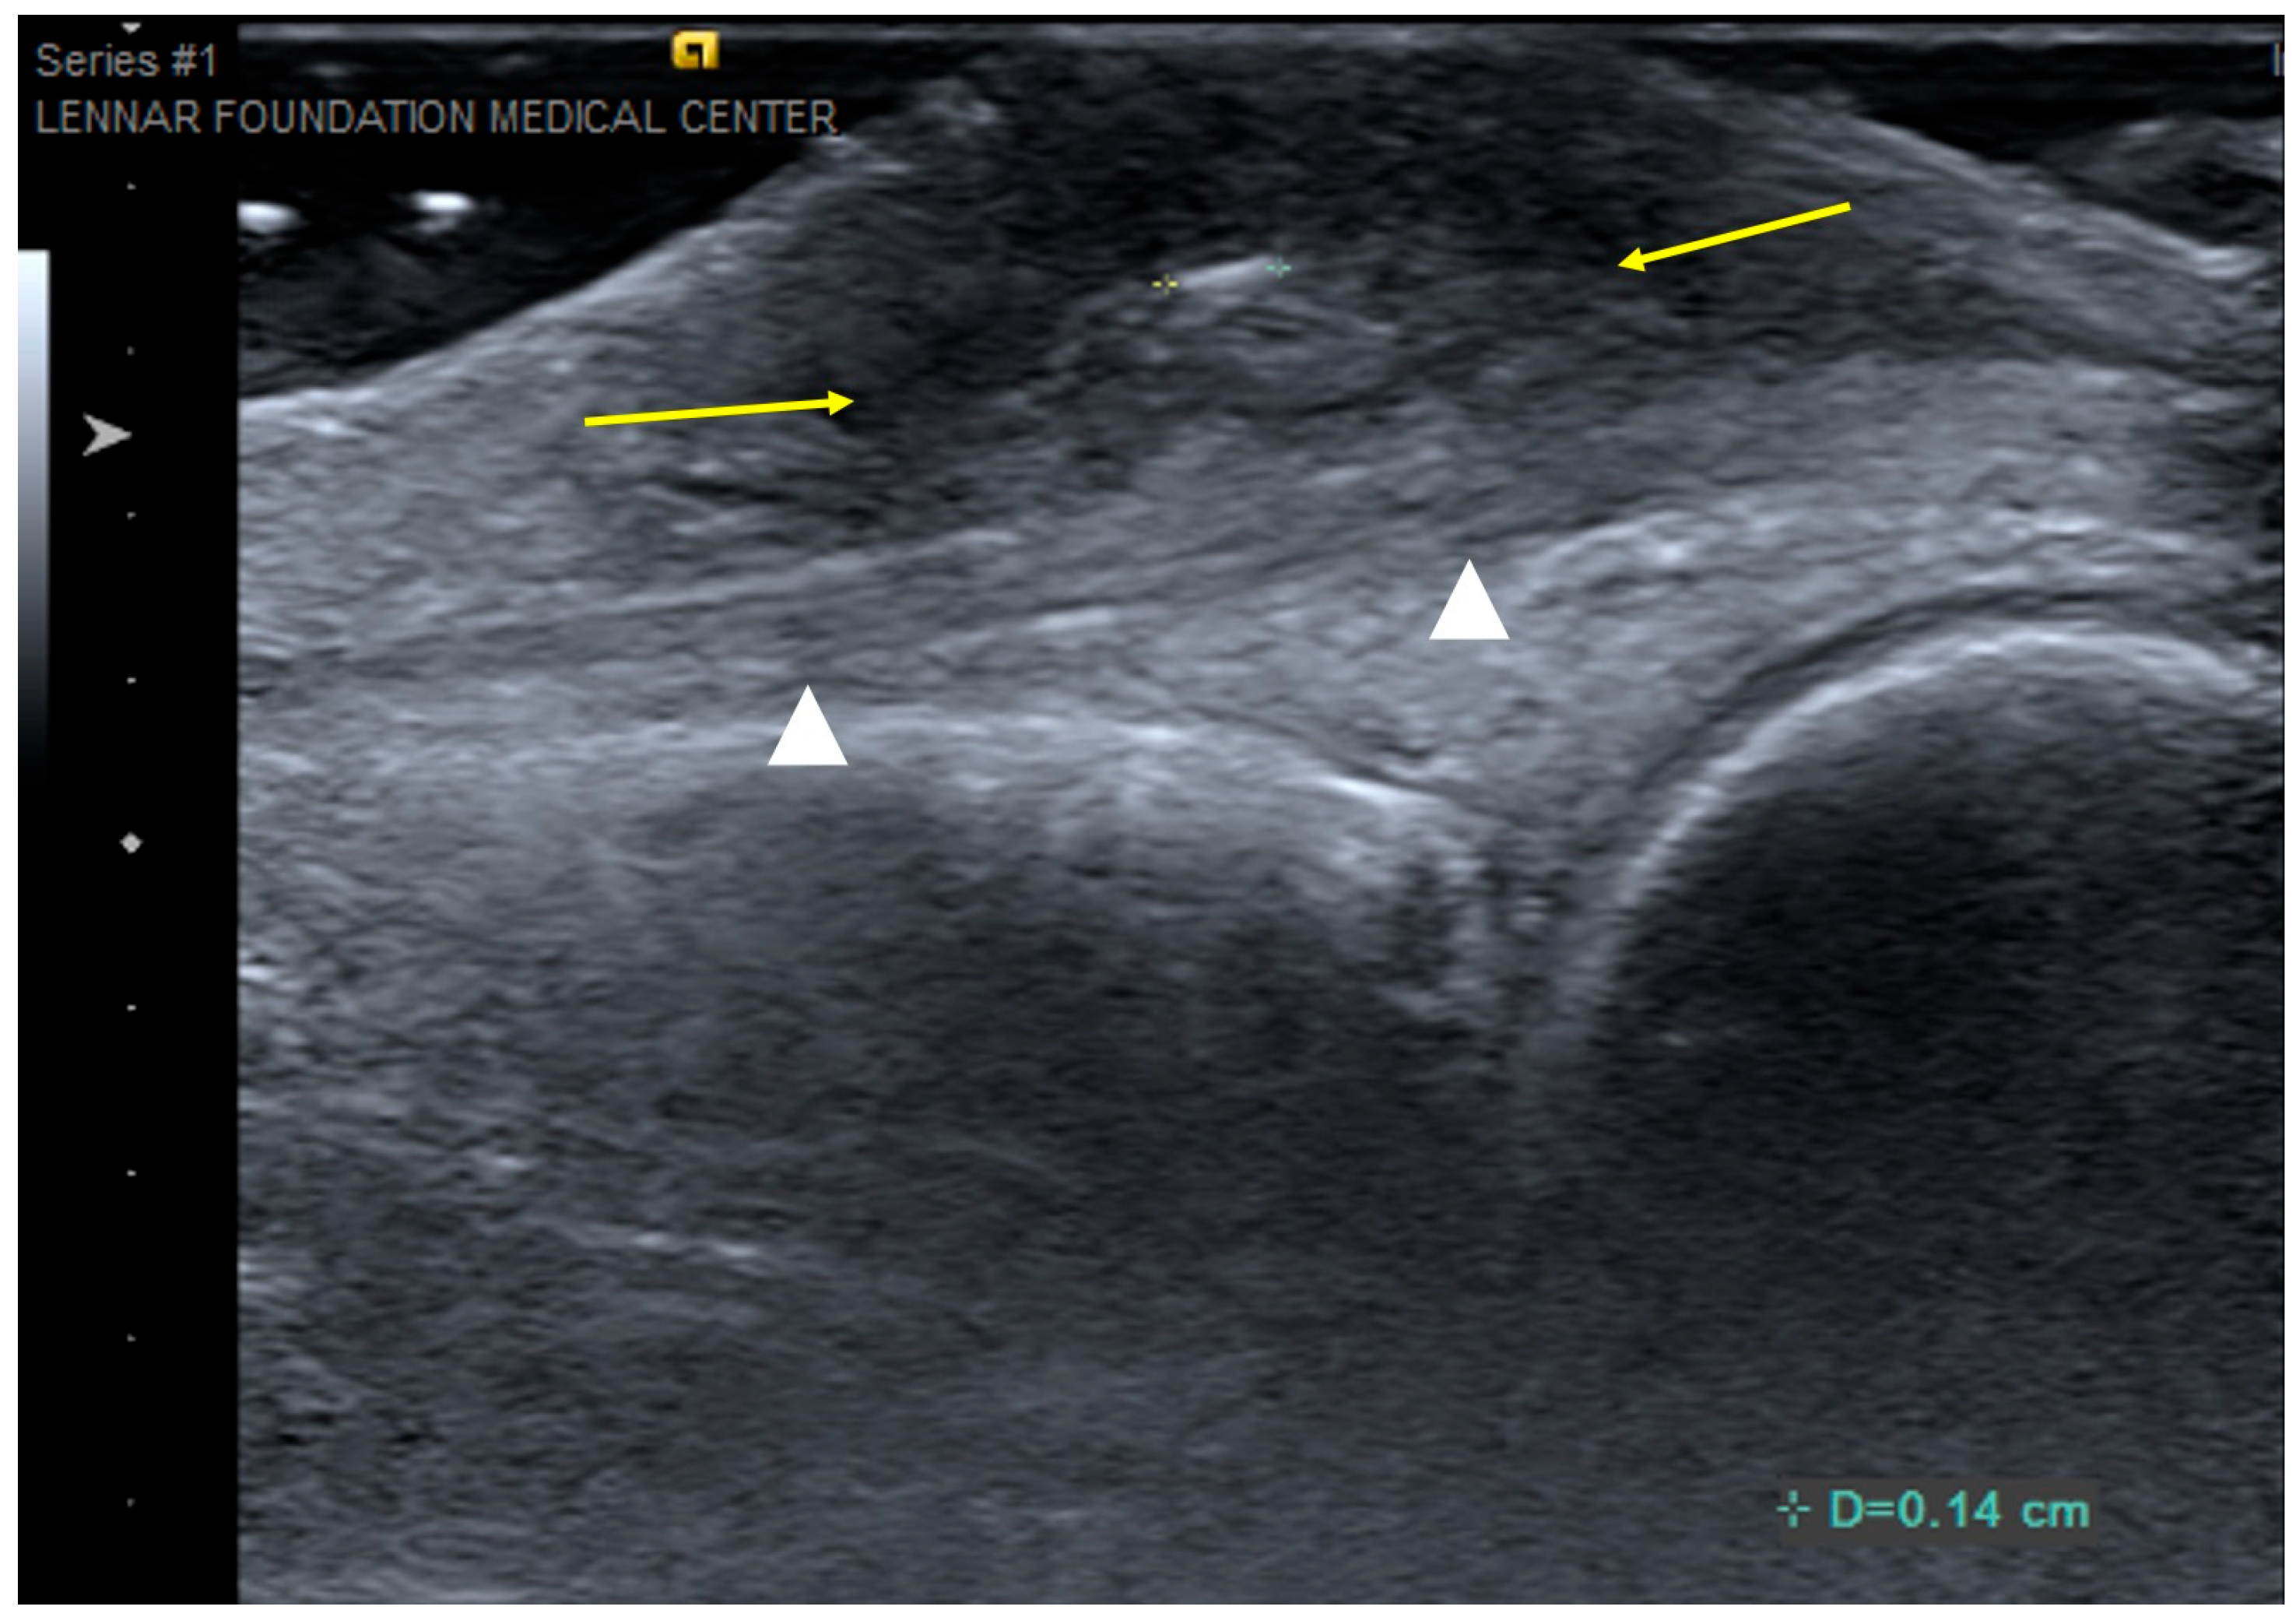

2.7. Superficial Fibromatoses

2.7.1. Clinical Features

2.7.2. Imaging Appearance